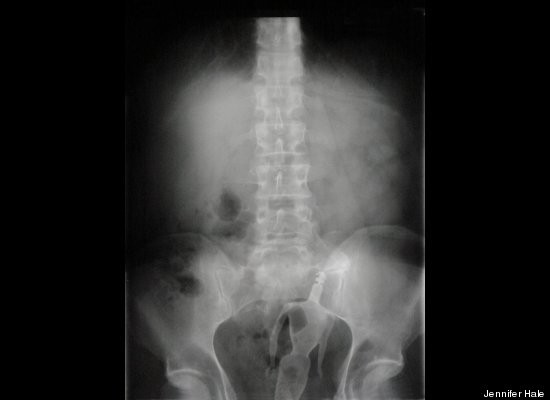

Người ta thường nghĩ chuyện đi cấp cứu do bị hóc vì vật lạ chỉ xảy ra với trẻ em, thế nhưng nhiều người lớn lại thường nuốt nhẫn cưới như một cách để giấu chúng. May mắn rằng việc này hầu như không để lại di chứng gì.